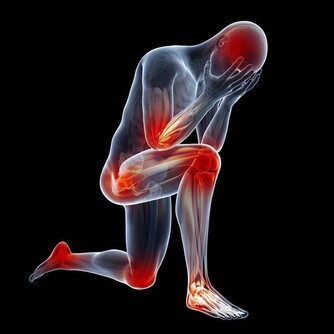

3. 它有助於消化

隨著年齡增長胃酸的量會下降,因此助消化對老人尤為重要。

超過30%的60歲以上者患有萎縮性胃炎,他們的胃內幾乎沒有胃酸。

而檸檬中的柑橘類黃酮有助於幫胃酸分解食物,從而改善整體的消化功能。

如果加熱水,助消化的效果更好。